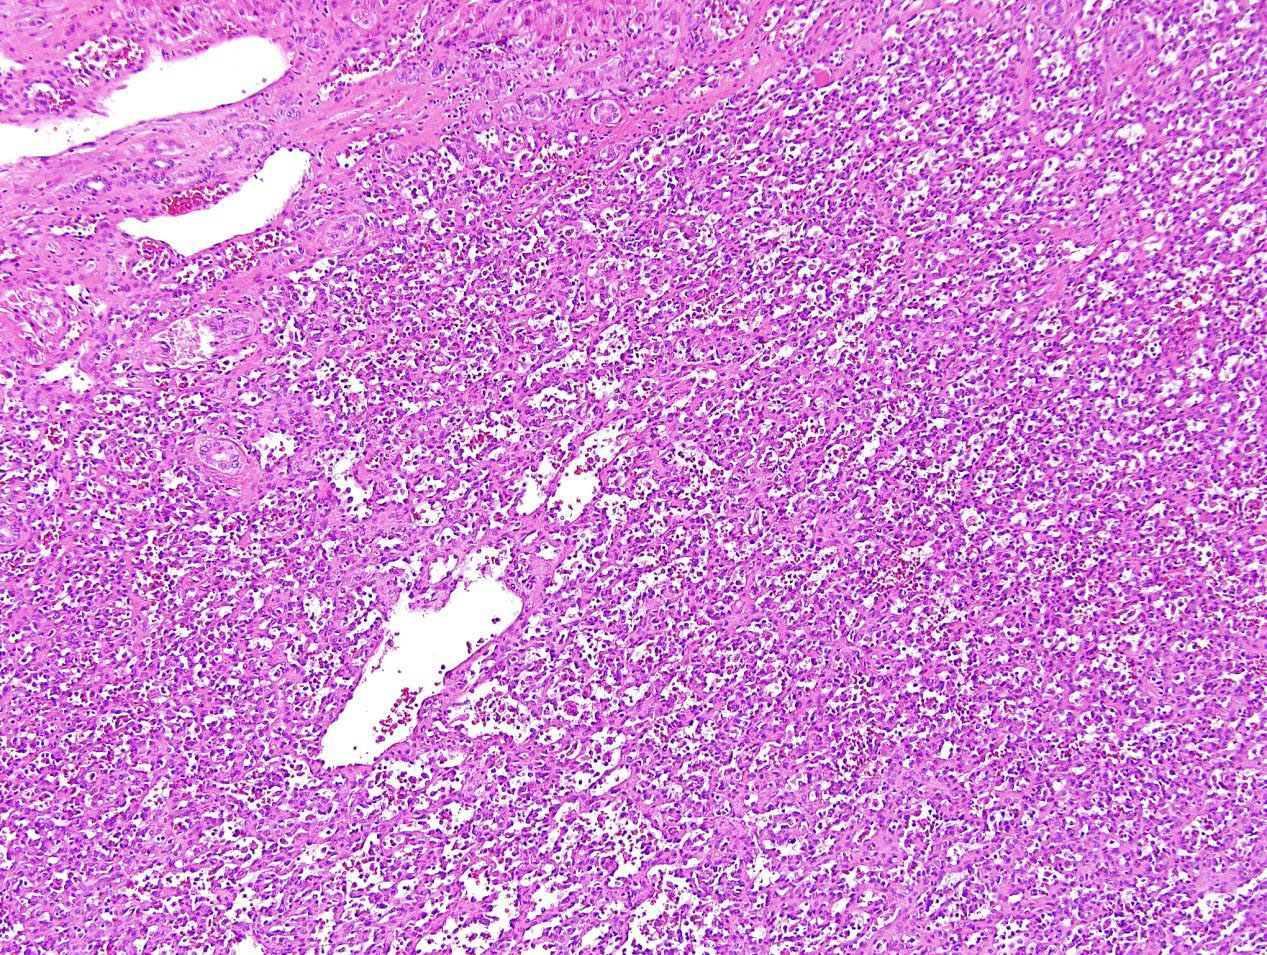

A 62 year old woman with a history of renal cell carcinoma removed years ago presented with a 2.4 cm liver mass found in CT during follow-up. A partial hepatectomy was performed.

Cut section reveals a 2.4 cm circumscribed mass with a gray-brown focally spongy appearance.

Hemangioma, anastomosing type.

Hepatic hemangioma is a common benign vascular neoplasm in both infants and adults that shares the same growth pattern and prognosis as its cutaneous counterpart. Based on its distribution, hemangioma can be classified as focal, multifocal, or diffuse. Most hepatic hemangiomas are of the cavernous type followed by the capillary type. Capillary hemangioma, including lobular capillary hemangioma (also known as pyogenic granuloma) commonly presents on the skin and mucosa, although rare liver or gastrointestinal tract examples have been reported. Capillary hemangioma is composed of a lobular proliferation of vascular channels with plump endothelial cells lining the vascular channels. Anastomosing hemangiomas in the liver, as seen in this case, are rare hepatic vascular neoplasms characterized by an interconnecting sinusoidal-like pattern of tightly packed capillary channels. The tumor appears well circumscribed grossly with a gray-brown focally spongy appearance in the liver. Low-power magnification shows a well-demarcated lesion with lobular architecture in the liver. At higher magnification the tumors consists of anastomosing sinusoidal capillary-sized vessels with scattered hobnail endothelial cells within a framework of non-endothelial supporting cells. No mitotic figures or necrosis are observed. Mild cytologic atypia is appreciated. Immunohistochemical stain for CD31 is diffusely positive.

The primary differential diagnosis of anastomosing hemangioma is angiosarcoma. Angiosarcoma of the liver and gastrointestinal tract is rare and behaves aggressively. The overall survival is poor and patients rapidly develop metastases and usually die within 6–12 months. Accurate diagnosis can be challenging, particularly if the patients have no history of exposure to specific toxins including thorium dioxide, arsenicals, and vinyl chloride monomer. Distinguishing anastomosing hemangioma from a well-differentiated angiosarcoma is challenging especially on small biopsies. Histologically, branching, jagged, slit-like vascular channels with prominent cytological alterations and a diffuse infiltrating border is characteristic of angiosarcoma, in contrast to the sharp demarcation, mild cytological atypia, and lack of mitotic figures in anastomosing hemangioma. The absence of multilayering of endothelial cells, high grade cytologic atypia, and mitotic activity coupled with circumscribed borders favor a benign process. Awareness of this entity and attention to cytological features and the overall lobular architecture are essential to avoid diagnostic errors.